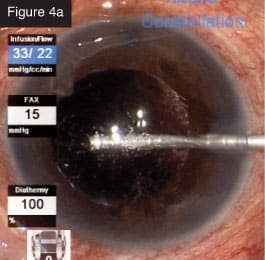

Bidirectional laser to breaks. CASE 4: Tractional detachment in silicone-filled eye. Silicone oil removal and injection can be done beautifully through small gauge with the CONSTELLATION® System. In this case, I entered through the limbus to remove droplets of emulsified silicone oil from the anterior chamber (Figure 4a). Then, I used forceps to lift the membrane that was causing the tractional detachment (Figure 4b). After lifting off the membrane, I was able to remove everything with the cutter (Figure 4c). I still utilize forceps in some cases, but I use them less often with this technology.

Removal of silicone droplets in anterior chamber with cutter.